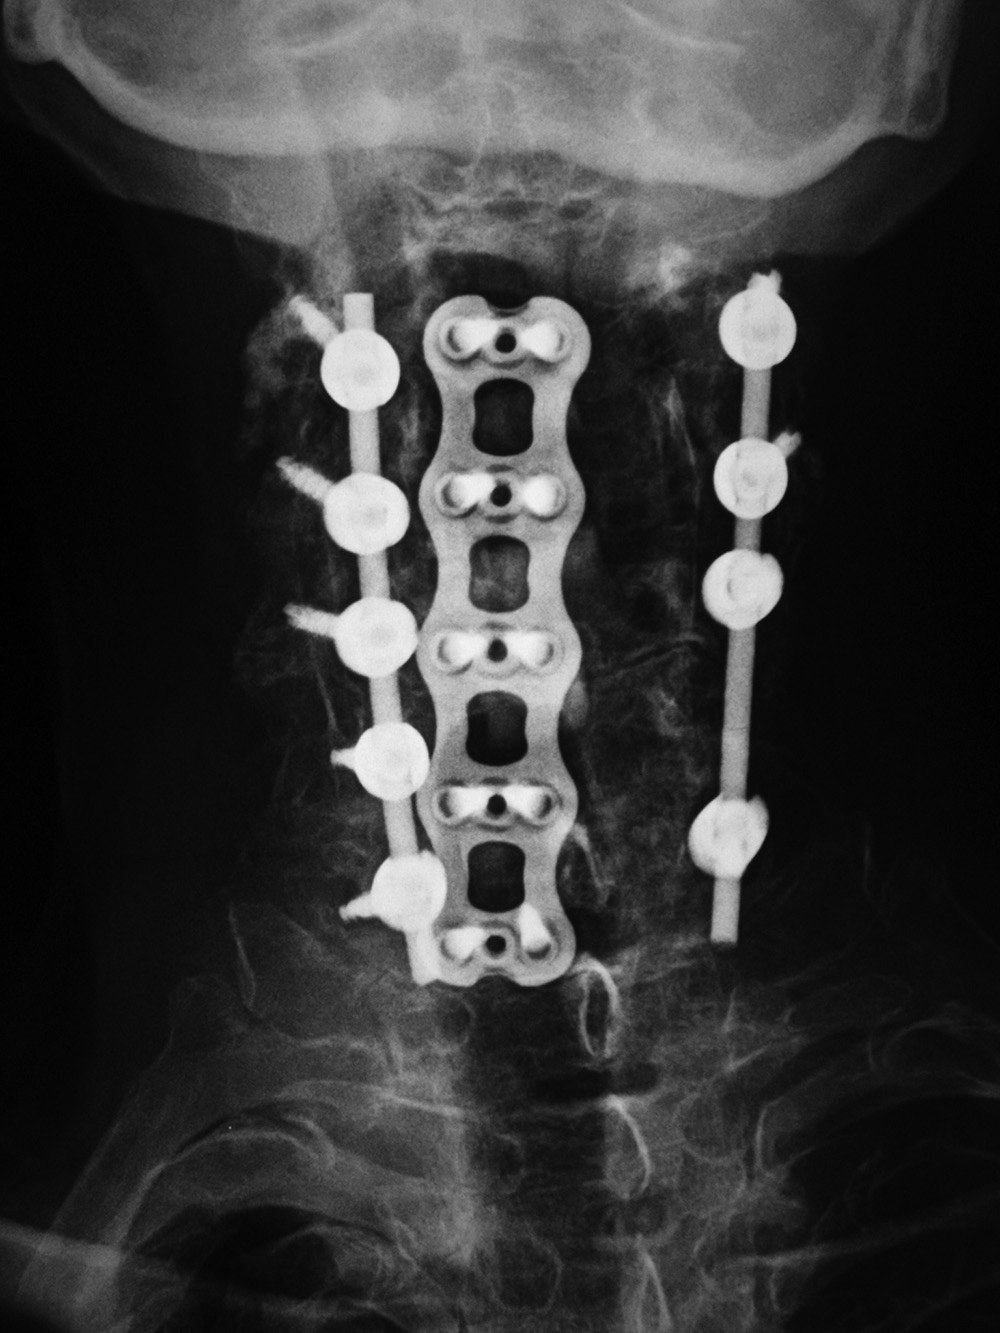

Anterior cervical fusion plate Cervical spine fusion cage and anterior cervical fixation plate Cervical spine intervertebral disk fusion cage

Anterior cervical fusion plate - AP view Anterior cervical fusion plate - lateral view Cervical spine fusion cage and anterior cervical fixation plate Cervical spine interverterbral disk fusion cage

53 year-old man with disk herniation. Anterior cervical fusion plate spans C3 to C6. Interbody disk bone plugs (spacers) are present at C3-4, C4-5, and C5-6.